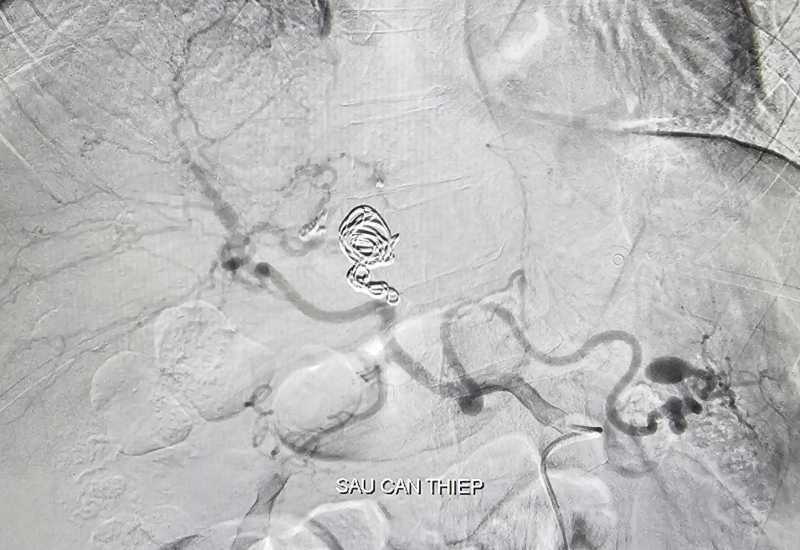

Kết quả ghi nhận ổ giả phình động mạch gan trái kích thước 15x22mm kèm phình động mạch gan trái. BS chọn lọc vào nhánh động mạch gan trái có tổn thương, tiến hành thả 3 vòng xoắn kim loại (coils) vào ổ giả phình, bơm hỗn hợp keo sinh học bít hoàn toàn túi phình. Sau 90 phút can thiệp, bệnh nhân ổn định được chuyển khu hậu phẫu theo dõi. Hiện bệnh nhân tỉnh, tiếp xúc tốt, niêm hồng, hết đau bụng, sinh tồn ổn định.